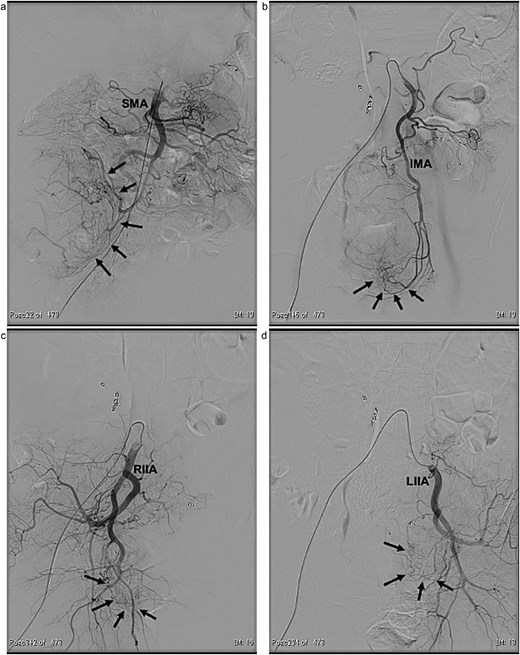

In 2011, a male patient in his 60s presented to the emergency department with loss of consciousness. His blood glucose level was 20 mg/dL. Contrast-enhanced computed tomography (CT) revealed a large tumour measuring 20 cm in diameter (Fig. 1). Primary surgery was performed and the tumour was diagnosed as an SFT histopathologically. Five years later, contrast-enhanced CT revealed a 4-cm tumour in the lower abdomen. His blood glucose levels were normal. A second surgery was performed; the tumour was excised, and several disseminated nodules were cauterized. Histology revealed that the tumour was an SFT. Eight years later, the patient presented with loss of consciousness. Laboratory data revealed a blood glucose level of 28 mg/dL. Contrast-enhanced CT revealed multiple tumours measuring 3–14 cm in diameter, spread within the abdominopelvic regions (Fig. 2). To prevent excessive intraoperative haemorrhage, preoperative TAE was performed on two larger tumours. Angiography revealed that the large tumour in the right lower abdomen was supplied by a branch of the superior mesenteric artery, whereas the pelvic tumour was supplied by branches from the inferior mesenteric and bilateral internal iliac arteries (Fig. 3). Super-selective catheterization and embolization of the vessels were performed. One week after embolization, a third surgery was performed. Nine tumours were resected. The operative time was 177 min, and the estimated blood loss was 620 mL. Histologically, part of the rectal wall showed necrosis. The tumour comprised spindle cells exhibiting a ‘patternless’ arrangement in a collagenous matrix (Fig. 4a). Immunohistochemical staining was positive for CD34, CD99, Bcl-2, and STAT6, which confirmed the diagnosis of recurrent SFT (Fig. 4b and c). The Ki-67 labelling rate was ~10% in the highly labelled regions. The tumour was also positive for insulin-like growth factor-II (Fig. 4d). After surgery, blood glucose levels completely stabilized. The patient developed a paralytic ileus that resolved spontaneously and was discharged 13 days after surgery. The patient was well, with no recurrence noted during the 10-month follow-up period.

Angiographic findings. The large tumour (arrows) located in the right lower abdomen was supplied by a branch arising from the superior mesenteric artery (SMA) (a). The pelvic tumours (arrows) were supplied by branches arising from both the inferior mesenteric artery (IMA) (b) and the bilateral internal iliac arteries (RIIA and LIIA) (c and d).